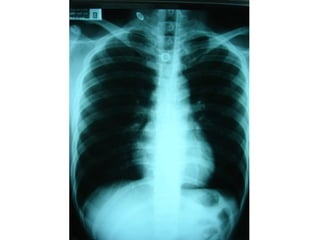

หญิงไทย 28 ถูกแฟนยิง แล้วแฟนนำาส่งโรงพยาบาลใน 20 นาที

ที่ห้องฉุกเฉิน BP 0, PR 0, RR เฮือก

• Secondary survey

HEENT : no open wound

Chest : equal breath sound , heart normal

s1s2 , no murmur

Abdomen : voluntary guarding

PR : blood

• Adjuncts to secondary survey

- Esophagogram

- CT chest and whole abdomen c IV

contrast